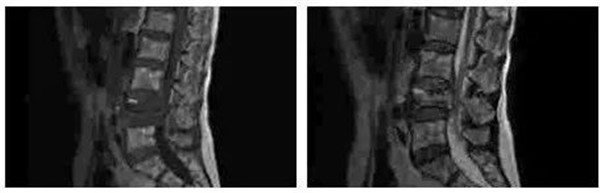

患者史某,女,59岁,以不慎摔倒后至腰背部疼痛3小时为主诉入我院骨四科。查体后发现患者腰椎活动受限,腰3-5棘突间隙压痛阳性,叩击痛阳性,双侧椎旁阳性,双侧下肢直腿抬高试验阴性,双下肢肌力、肌张力未见异常,双下肢皮肤感觉正常。后经影像学进一步检查明确患者为腰4椎体爆裂性骨折,骨四科团队经过讨论后决定为患者实施“后入路腰4椎体爆裂性骨折CBT螺钉固定、椎管减压、小关节融合术”。术后患者恢复良好。

术前MR